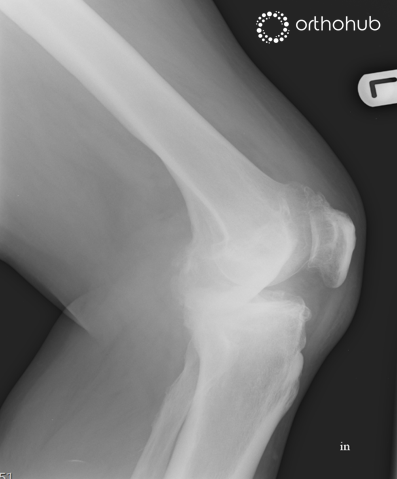

The radiographs are of a 62-year-old male, otherwise fit and well, who presents with worsening pain and stiffness in the joint. This is now increasingly limiting his day-to-day activities; including both his keen hobby of golf, and his work as a train conductor.

He reports having always ‘been a little bow-legged’ but was pain free until about 5 years ago. Physiotherapy and analgesia have failed to improve his symptoms. He takes no regular medication.

Clinical examination demonstrates pain and crepitus through the arc of motion, with marked laxity on varus stressing. The medial soft tissues are tight, and the patella tends to track medially. He is keen on a definitive surgical solution.